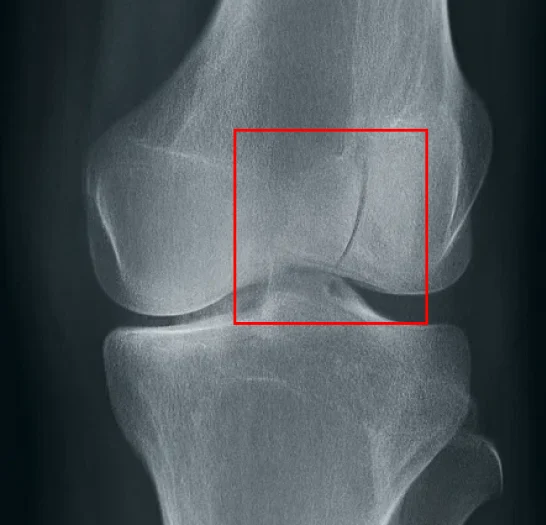

Musculoskeletal X-ray Annotation & Segmentation

Pareidolia Systems delivers expert musculoskeletal X-ray annotation and segmentation services for AI-powered orthopedic imaging. Our combination radiologist & clinical annotators workflow ensures precise fracture, implant, and joint labeling with rigorous quality control. We create structured, AI-ready datasets that accelerate medical imaging innovation, improve diagnostic accuracy, and support advanced machine learning models.